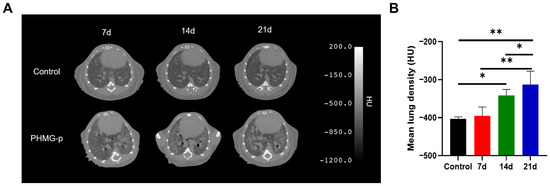

Background/Objectives: Pulmonary fibrosis is a progressive and fatal lung disease with limited diagnostic and therapeutic options. Fibroblast activation protein (FAP) has emerged as a promising molecular imaging target for the non-invasive assessment of fibrotic activity. This study aimed to evaluate the diagnostic feasibility of [68Ga]Ga-FAP inhibitor (FAPI) and [18F]fluorodeoxyglucose ([18F]FDG) positron emission tomography (PET) for imaging pulmonary fibrosis in a mouse model. Methods: A pulmonary fibrosis model was established by intratracheal administration of polyhexamethylene guanidine-phosphate (PHMG-p) to C57BL/6 mice. Fibrosis severity was quantified by the Ashcroft scoring system using hematoxylin and eosin and Masson’s trichrome staining and evaluated by computed tomography (CT) imaging at 7, 14, and 21 days after PHMG-p exposure. PET imaging was performed, and ex vivo biodistribution was assessed after injection of [68Ga]Ga-FAPI-04 and [18F]FDG. Results: Histological analysis and Ashcroft scoring revealed greater fibrosis severity in the PHMG-p-treated group. Western blot analysis demonstrated upregulation of FAP expression after PHMG-p exposure. CT showed increased mean lung density, while [68Ga]Ga-FAPI-04 PET revealed significantly elevated pulmonary uptake of [68Ga]Ga-FAPI-04 in the PHMG-p-treated group compared with the controls. [18F]FDG PET imaging also showed higher uptake of [18F]FDG in the PHMG-p-treated group than in the controls. Ex vivo biodistribution confirmed greater [68Ga]Ga-FAPI-04 accumulation in the lungs of PHMG-p-treated mice. Conclusions: [68Ga]Ga-FAPI-04 PET serves as a sensitive imaging biomarker for evaluation of fibrotic activity in PHMG-p-induced pulmonary fibrosis and complements [18F]FDG PET for assessing disease progression and therapeutic response. Full article

Figure 1